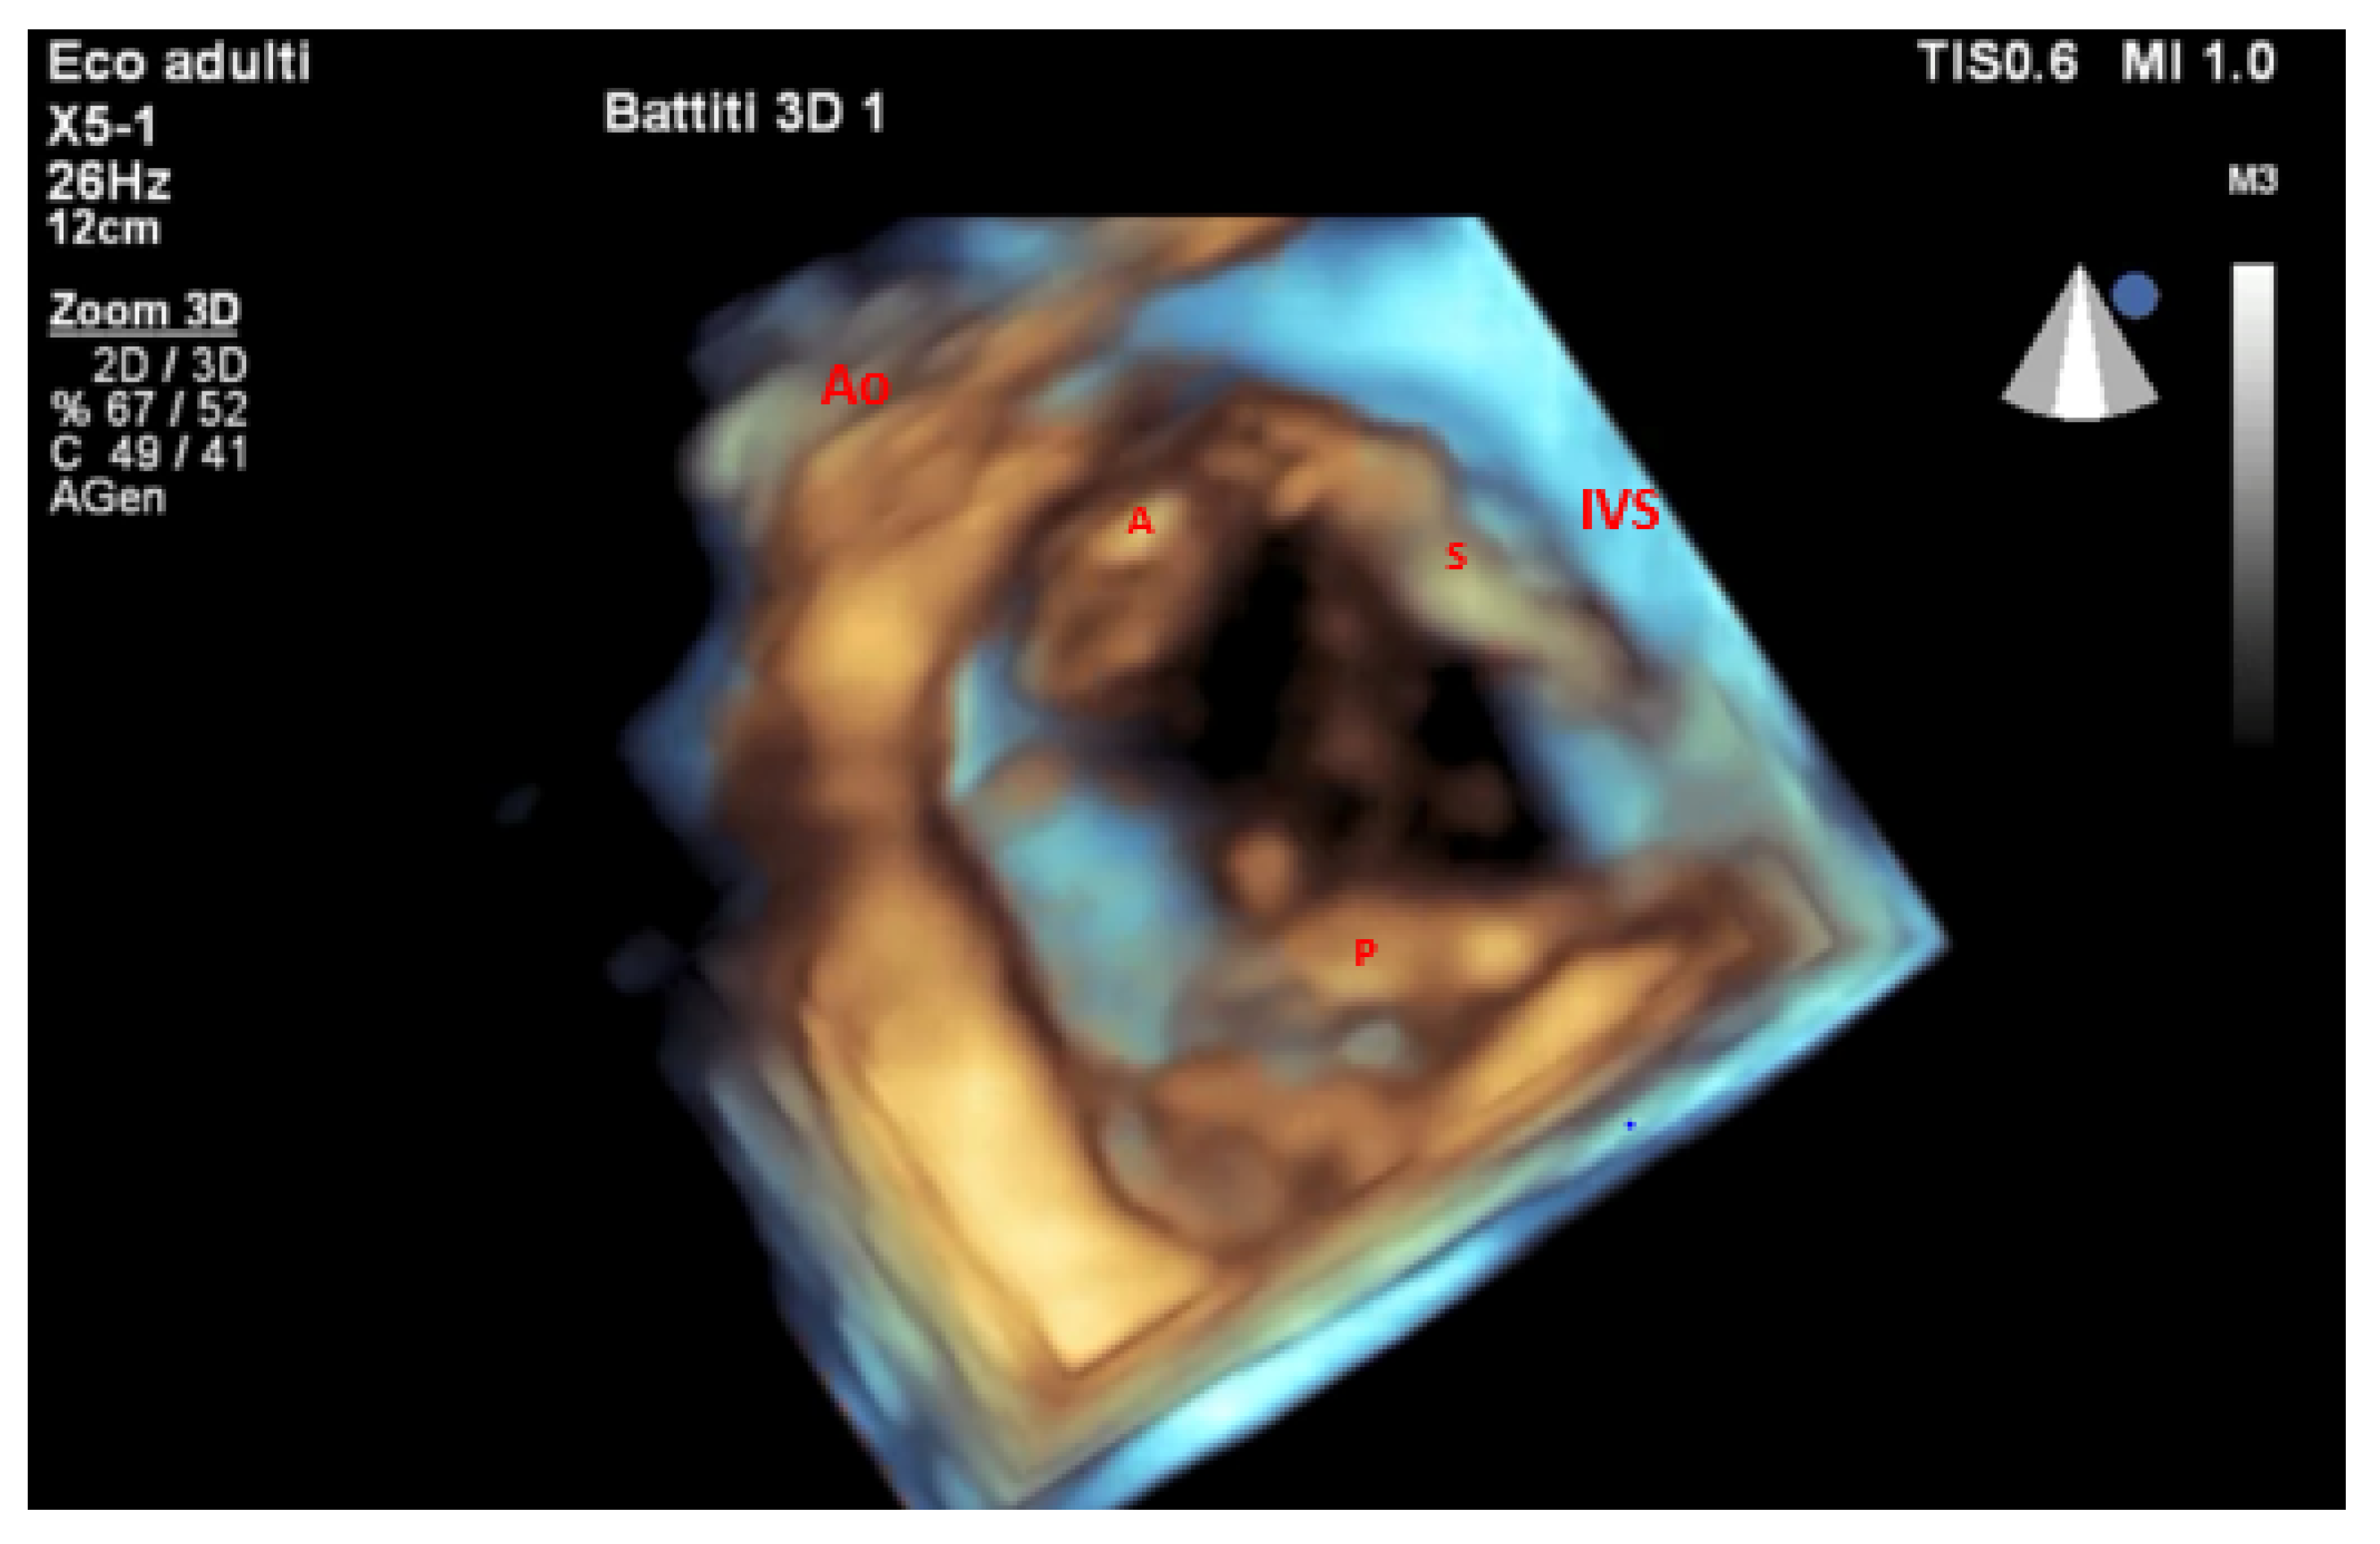

- Lang, R.M.; Badano, L.P.; Tsang, W.; Adams, D.H.; Agricola, E.; Buck, T.; Faletra, F.F.; Franke, A.; Hung, J.; Pérez De Isla, L.; et al. EAE/ASE Recommendations for Image Acquisition and Display Using Three-Dimensional Echocardiography. J. Am. Soc. Echocardiogr. 2012, 25, 3–46. [Google Scholar] [CrossRef] [PubMed]

- Muraru, D.; Gavazzoni, M.; Heilbron, F.; Mihalcea, D.J.; Guta, A.C.; Radu, N.; Muscogiuri, G.; Tomaselli, M.; Sironi, S.; Parati, G.; et al. Reference Ranges of Tricuspid Annulus Geometry in Healthy Adults Using a Dedicated Three-Dimensional Echocardiography Software Package. Front. Cardiovasc. Med. 2022, 9, 1011931. [Google Scholar] [CrossRef]

- Cotella, J.I.; Blitz, A.; Clement, A.; Tomaselli, M.; Muraru, D.; Badano, L.P.; Sauber, N.; Font Calvarons, A.; Degel, M.; Rucki, A.; et al. Three-Dimensional Transthoracic Echocardiography for Semiautomated Analysis of the Tricuspid Annulus: Validation and Normal Values. J. Am. Soc. Echocardiogr. 2025, 38, 33–43.e3. [Google Scholar] [CrossRef]